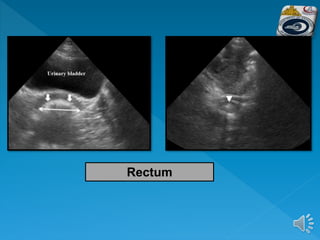

 The rectum is visualized through the filled

bladder